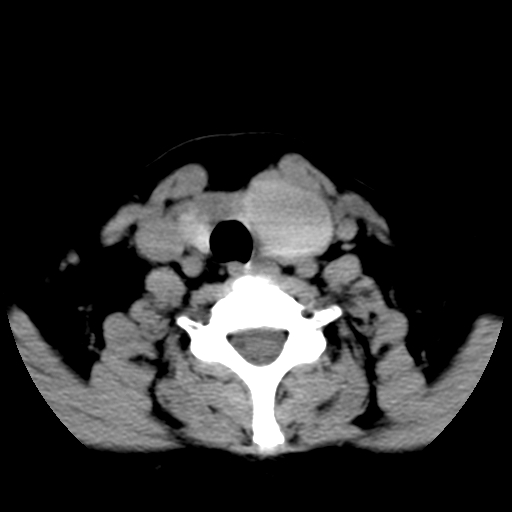

标题: CT25491:女,55岁,发现左侧甲状腺肿块一个月。 [打印本页]

标题: CT25491:女,55岁,发现左侧甲状腺肿块一个月。

女,55岁,发现左侧甲状腺肿块一个月,彩超示:甲状腺多发结节伴左叶结节液化。